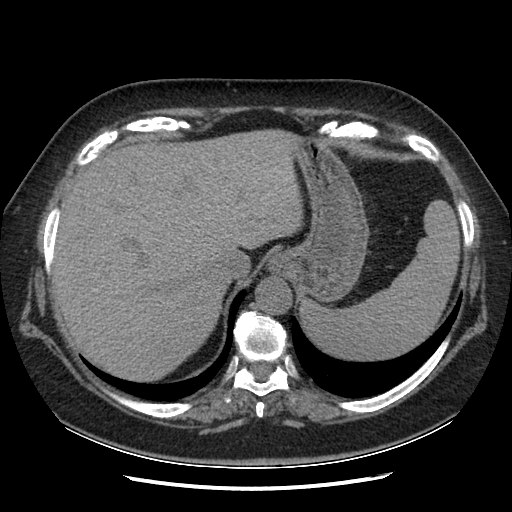

Original VENOUS CT scan

Full window (WL 1023.5, WW 4095 β†’ Low βˆ’1024, High +3071)

Actual HU range: [-160.0, 240.0]